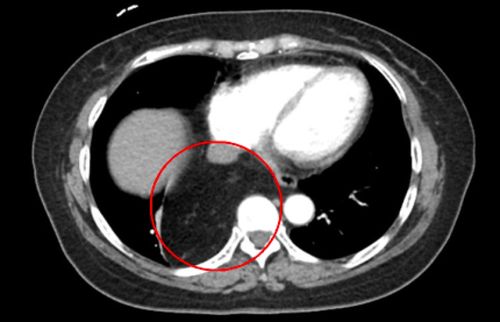

除了癌症,胃炎、胃溃疡等良性疾病也可能导致频繁打嗝。甚至在某些化疗过程中,或肿瘤转移至膈肌附近的情况下,也可能引发顽固性的打嗝,这种情况多见于晚期癌症患者。